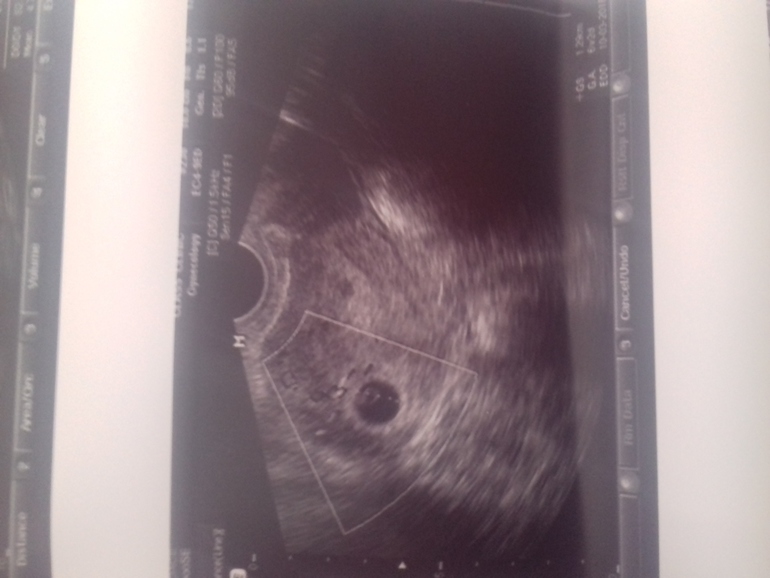

Договорились вместе ждать, так вот я сегодня утром тоже сходила, но не потому что не дождалась, а неправильно посчитала, 7 недель и 7-ая - не одно и то же, торможу)))

Сб +, ктр 2 мм